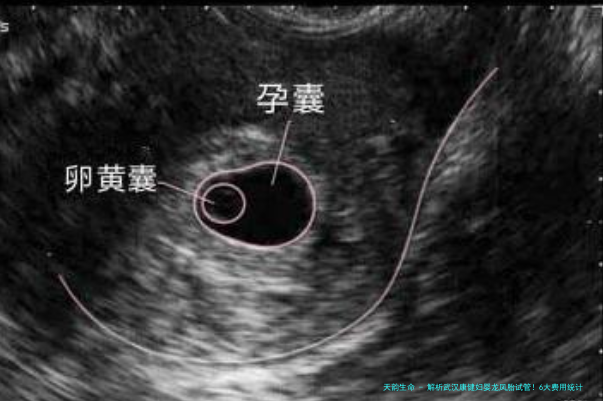

在试管移植后,医生都会为病人开黄体支持药物来保胎,有吞服的、肌肉注射的和塞阴道的,并安排病人在移植后两周到医院检查是否有未成功怀孕,此项费用可能会在数千个元到上万元。